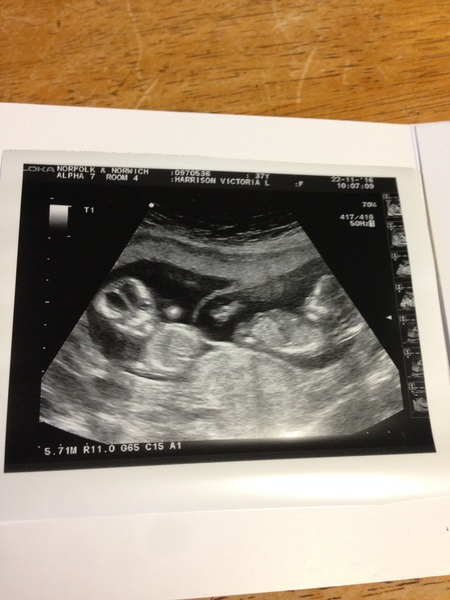

MumofthreeandBean · 22/11/2016 16:50

moose lovely pic!! ❤️️

We had a shock!! See pic!!!

Truly I knew but didn't think I was right!

Dates changed by 2 days, so 13.1, due 29th may

More twins!!!!! Amazing and great pic!!! Brilliant!!!

Wow, congratulations - twins!! Do they run in your family? How did you guess?

moose thanks, sonographer said it's very hard to get pic of both,she gave it to me free😂

oliver I was a twin, my brother died before birth. I've had a feeling all along, been so nautious basically from conception!! Big bump already and I'm an older mum and had 3 babies already - that increased my chances!